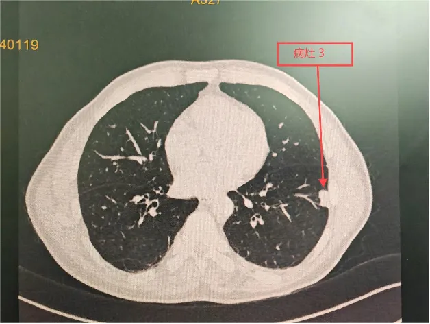

治疗前

治疗1月后

明确诊断后,主管医师予以相应的治疗方案,程大叔的咳嗽、胸痛症状迅速得到了缓解;1月后复查胸部CT,提示肺部阴影较前明显吸收;程大叔悬着的心,终于放下了。